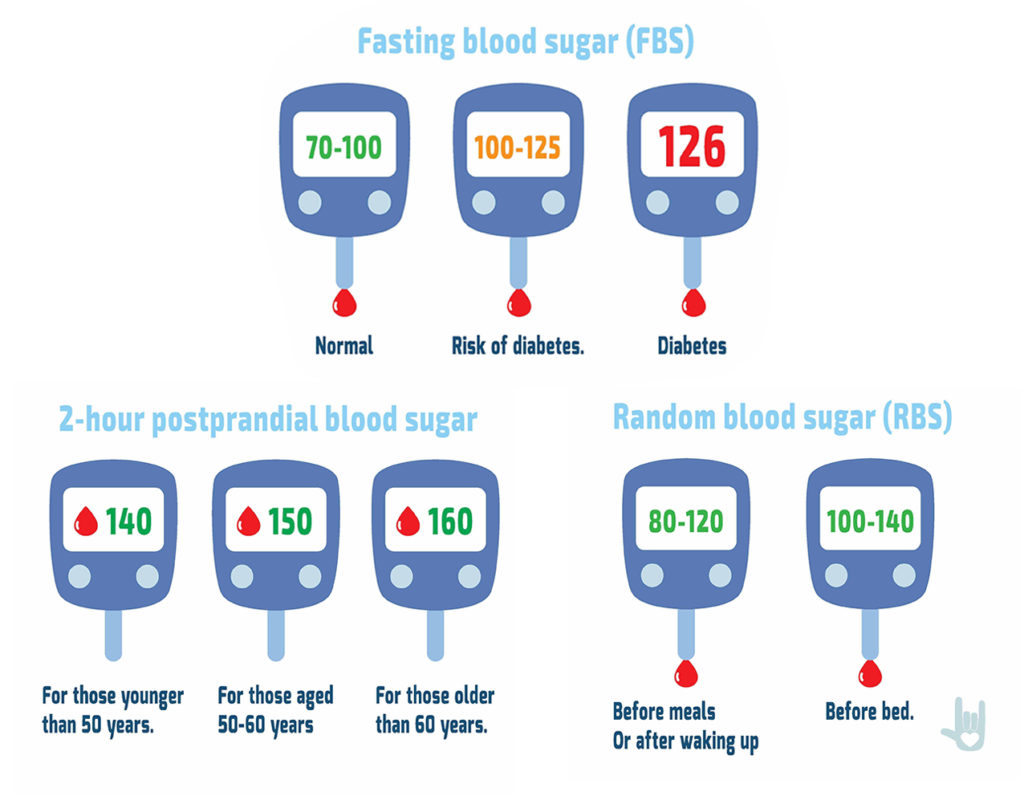

Normal Blood Sugar Level Normal Blood Sugar Level

Normal Glucose Levels Chart